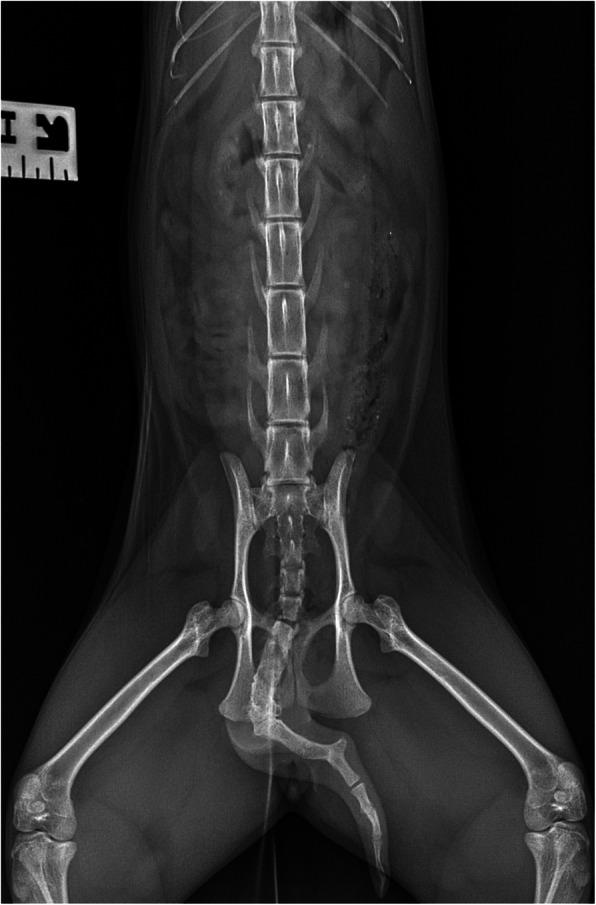

年轻雌性猫中骨盆入口处交叉异位融合肾、非典型门静脉和尾骨变形。

Crossed renal ectopia with fusion in a pelvic inlet area, atypical portal vein and coccygeal deformation in a young female cat.

The case report describes a rare congenital anomaly, crossed fused renal ectopia (CFRE), with coexistence of two other abnormalities - atypical portal vein and coccygeal vertebrae malformation in a domestic cat. The concomitance of those 3 congenital defects has not been described previously.

CASE PRESENTATION

An 8-month-old female, domestic cat suffering from chronic diarrhea was referred to the diagnostic imaging unit. The patient showed no other clinical symptoms. An abdominal ultrasonographic examination was performed in order to evaluate the condition of abdominal organs, particularly the gastrointestinal tract. The ultrasound examination showed an ectopic duplex kidney at instead of kidneys in their typical location. Computed tomography (CT) with angiographic phase and excretory urography was requested to evaluate the condition of the kidneys and ureters. The final diagnosis was CFRE, atypical portal vein and coccygeal deformation in an asymptomatic cat with no changes in renal function and normal blood parameters.

本病例报告描述了一种罕见的先天性异常,即交叉融合性异位肾(CFRE),同时还存在另外两种异常——非典型门静脉和尾骨椎畸形,这些异常均发生于一只家猫。此前尚未有描述过这 3 种先天性缺陷同时存在的情况。

病例介绍

一只 8 月龄雌性家猫因慢性腹泻被转诊至影像诊断部门。该猫除腹泻外无其他临床症状。进行了腹部超声检查以评估腹部器官,特别是胃肠道的情况。超声检查显示异位双肾盂,而非在其典型位置的双肾。为评估肾脏和输尿管的情况,请求进行 CT 增强扫描和排泄性尿路造影。最终诊断为 CFRE、非典型门静脉和尾骨畸形,无症状猫无肾功能和血液参数变化。